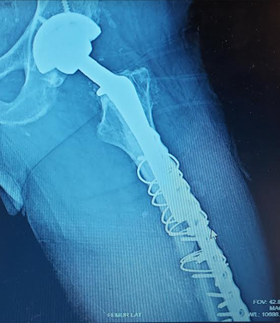

Second fixation, that's a lot of metal, including a few broken screws. Second photo shows healing callus